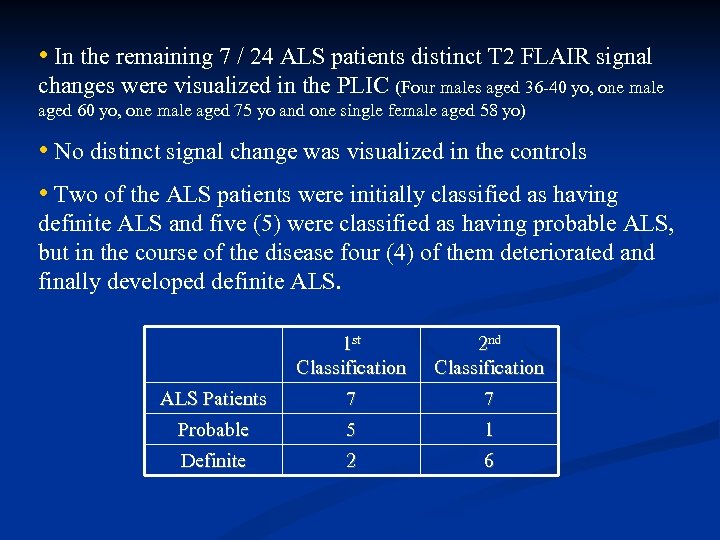

• In the remaining 7 / 24 ALS patients distinct T 2 FLAIR signal changes were visualized in the PLIC (Four males aged 36 -40 yo, one male aged 60 yo, one male aged 75 yo and one single female aged 58 yo) • No distinct signal change was visualized in the controls • Two of the ALS patients were initially classified as having definite ALS and five (5) were classified as having probable ALS, but in the course of the disease four (4) of them deteriorated and finally developed definite ALS. 1 st Classification 2 nd Classification ALS Patients 7 7 Probable 5 1 Definite 2 6

• In the remaining 7 / 24 ALS patients distinct T 2 FLAIR signal changes were visualized in the PLIC (Four males aged 36 -40 yo, one male aged 60 yo, one male aged 75 yo and one single female aged 58 yo) • No distinct signal change was visualized in the controls • Two of the ALS patients were initially classified as having definite ALS and five (5) were classified as having probable ALS, but in the course of the disease four (4) of them deteriorated and finally developed definite ALS. 1 st Classification 2 nd Classification ALS Patients 7 7 Probable 5 1 Definite 2 6